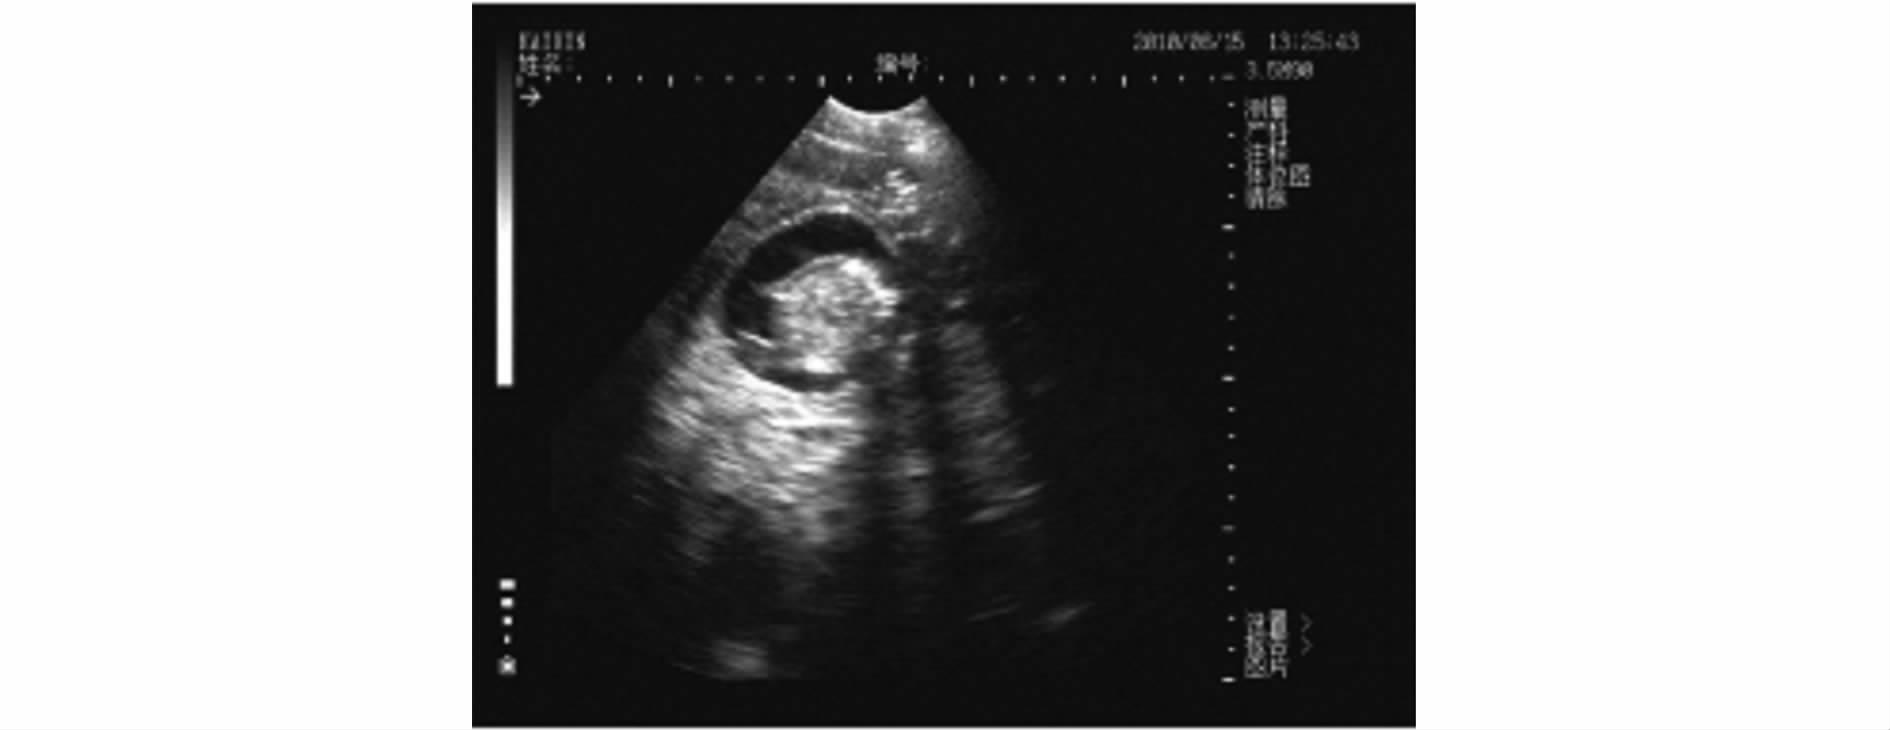

3.2.2 妊娠母猪 母猪妊娠的声像特征:妊娠初期子宫中出现孕囊,又称妊娠囊,内含初期胎水,量很少,对超声不产生反射,呈小的圆形暗区。在配种后19d、20d最早被扫查到时,暗区的直径在1.0cm左右,通常为一个暗区,有时可见2个或3个相邻的暗区(见图9),位于膀胱暗区的前下方或下方。为了便于B超操作者对B超成像进行有效准确地判断,作者专门附了一张母猪妊娠剖面与B超影像对比图(见图10)。

图9 母猪妊娠19日龄B超影像